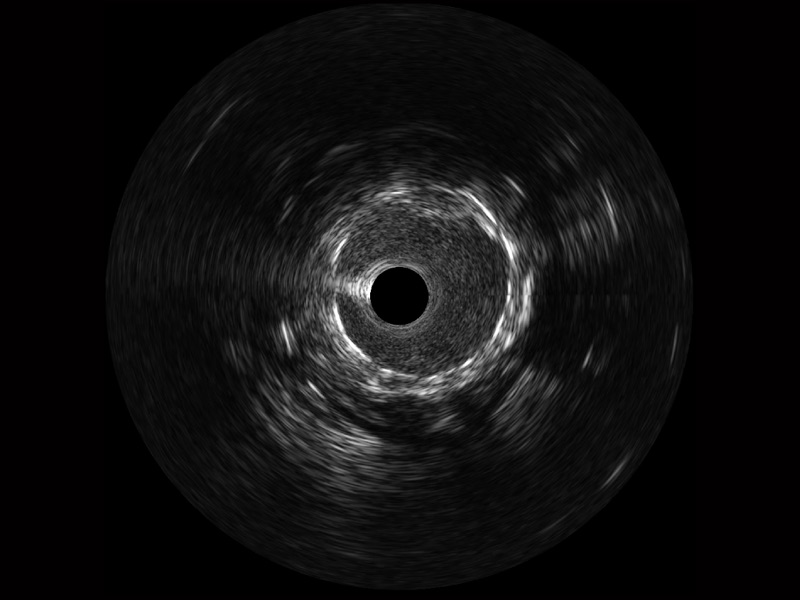

• 传统IVUS图像

对比传统IVUS导管成像,环球UG官网宽频IVUS图像的近场支架梁显影更细腻,远场中膜外血管仍清晰可辨,兼顾远中近,兼顾分辨力与穿透深度